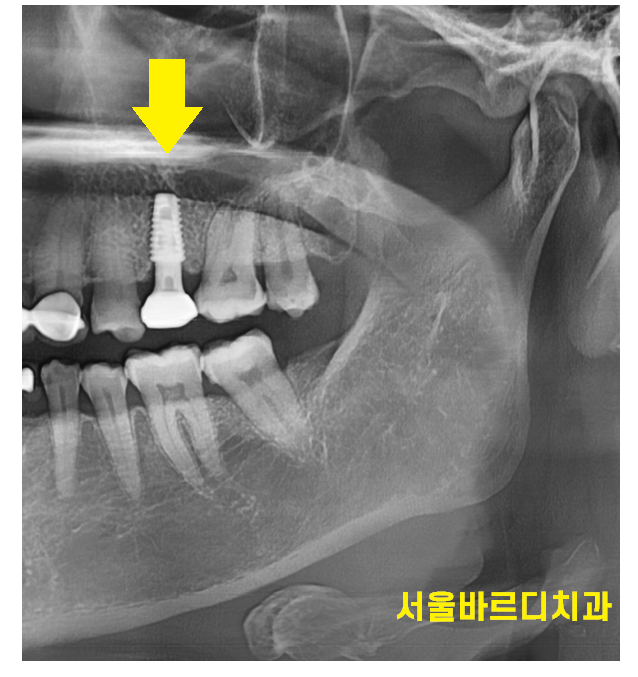

앞니 치료는 심미적인 이유로 브릿지를 추천하기도 합니다.

앞니 뼈가 얇아 고난이도 수술 부위이기도 하고

시간이 지나 앞니 뼈가 꺼지면 안예쁜 경우가 있거든요~

임플란트는 뼈에 심는건데

공간이 안나오면 브릿지로 대체하죠~